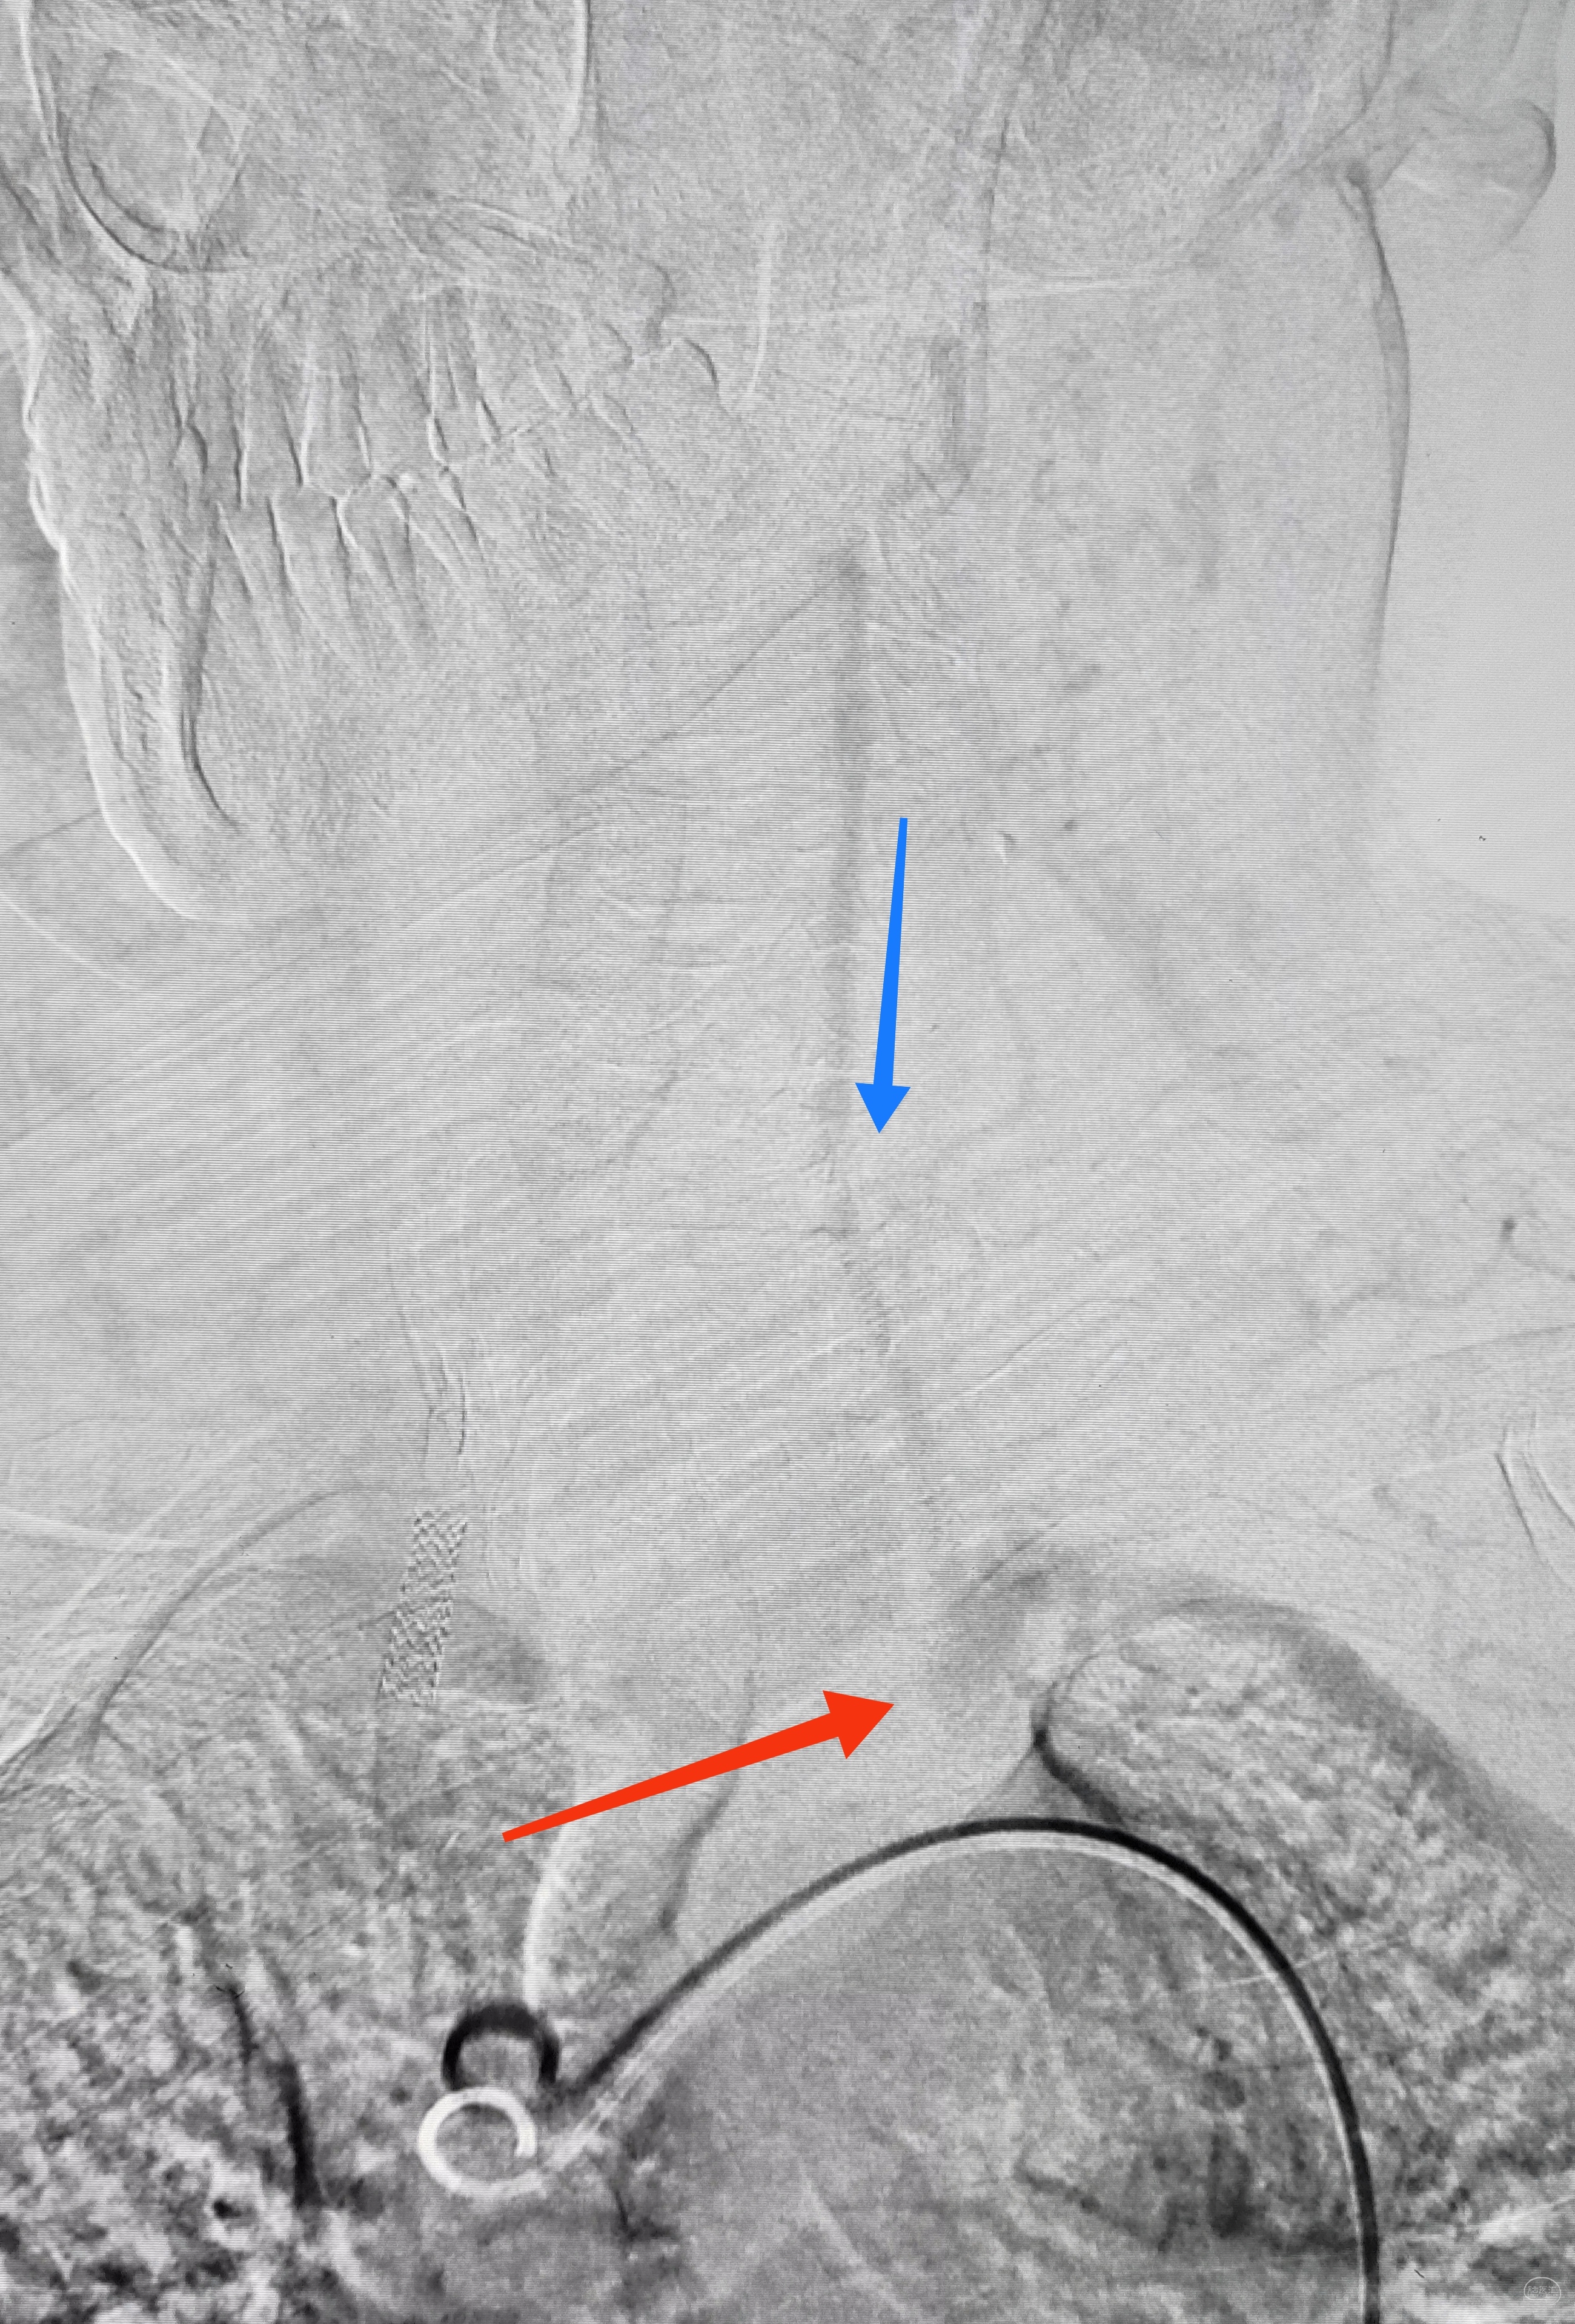

造影显示了依旧闭塞的左侧锁骨下动脉,依旧的逆向盗血

艰苦卓绝的吃线过程,此处心中浮现出一万个草泥马,最终,多角度+超选造影,验证真腔

小球囊+大球囊,梯度预扩

一切看似理想,一切看似简单,诡异的事情还是发生了,8F导引导管死活无法进入左侧锁骨下动脉,各种方法尝试个遍:泥鳅走远,单弯挂口,Sim挂口,屡战屡败(水平退步明显,不应该啊,夹层?),因为怕折腾,因为想安全,怕进假腔,弄出夹层。索性换一个思路:空中接力,构建桡-股动脉大环线

泥鳅两段露头,8F导引导管沿泥鳅攀爬,一把干到左侧肱动脉为止

6F导引导管造影确认支架置入部位

支架导引导管内先通过,再回撤技术,顺利释放雅培9×29球扩支架